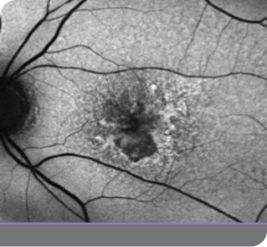

Case study of a GATHER2 clinical trial patient

This is the experience of a 79-year-old female with bilateral GA who reported good vision but said she needed a magnifying glass to read the newspaper

The patient was enrolled in the IZERVAY clinical trial for treatment of the right eye, and the left eye was observed. 2.5 years after initiating treatment in the right eye, product became available and the left eye was treated with IZERVAY.

• Baseline vision was 20/40 OD and 20/63 OS

• In the right eye, there was a 4.01-mm2 nonsubfoveal GA patch

• In the left eye, there was a 0.77-mm2 patch of GA inferiorly

• Hyperfluorescence at the lesion border signifies disease activity and is an indicator of progression

In this patient, IZERVAY slowed lesion growth over time

IZERVAY-treated right eye (OD)

Untreated left eye (OS)

1y 1m

2y 11m

Left eye (OS) treated with IZERVAY at 2.5 years

OD=oculus dexter; OS=oculus sinister.

Images courtesy of Dr. Beth Richter.

This is an individual patient case study. It should be interpreted with caution and cannot be considered conclusive. Individual results may vary. In the GATHER trials, sham was used as the comparator.